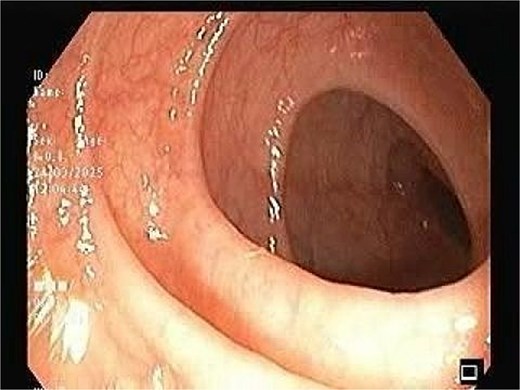

CT scan of the pelvis suggested a chronic inflammatory process. An MRI Perianal Region/Fistulogram (Fig. 1) was done and the findings were as follows: A possible fistulous tract was observed in the right perianal region, with a distal blind end in the intergluteal cleft. The presence of a fistulous tract and its extent was unclear. MRI findings could not differentiate between infectious, inflammatory, or neoplastic processes but it can definitely point out the presence of an abscess, which was not the case in our patient. Owing to the difficulty in establishing the diagnosis a colonoscopy was done and the findings (Figs 2 and 3) were as follows: A semicircumferential area from 7 to 11 o’clock position with tiny erosions was noted, which extended 4 cm from the anal verge.

A possible fistulous tract was observed in the right perianal region, with a distal blind end in the intergluteal cleft. The fistulous tract does not involve the anal sphincter complex/levator ani muscle.

The image depicting normal colonic mucosa up to caecum with normal vascular pattern.

No ulcerations, strictures, or masses suggestive of malignancy were detected. Endoscopic biopsies from the area suggested no specific pathology. The colonic mucosa appeared normal beyond the affected area, making systemic inflammatory disease less likely.